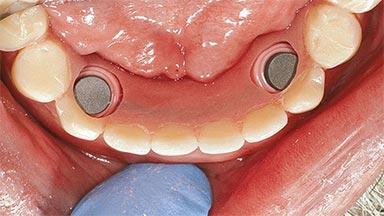

An 83-year-old man presented together with his caregiver at the dental department of the Medical University of Innsbruck, Austria with complaints of swelling in the right maxillary canine area and loss of retention of his 5-years-old mandibular denture. The patient had a significant medical history (20 years) of bipolar affective disorder with moderate depression (F 31.3) and dementia in Alzheimer’s disease (F 00.2). The patient had been in ambulant psychiatric therapy for his depressive illness for the past 20 years. He lived alone and had no children; his sister assisted with daily living. She reported that the patient exhibited compulsive hoarding behavior. In the previous two months, she had noted increasing disorientation and vertigo in the patient. She therefore accompanied him for a medical consultation at the Department of Psychiatry and Psychotherapy of the Medical University of Innsbruck. He was released home after a 6-week inpatient stay.